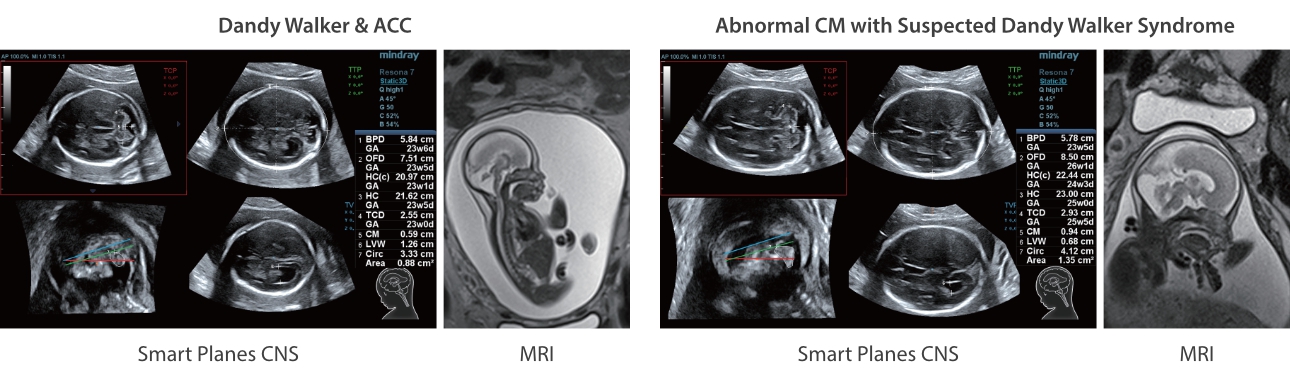

AdemÃĄs de una calidad superior de la imagen, el Resona 7 tambiÃĐn mejora las capacidades de investigaciÃģn clÃnica gracias al revolucionario V Flow para la evaluaciÃģn hemodinÃĄmica vascular y la adquisiciÃģn de planos mÃĄs inteligente a partir de un conjunto de datos 3D para el diagnÃģstico CNS fetal. Combinando el funcionamiento multitÃĄctil mÃĄs intuitivo basado en gestos y todas las funciones clÃnicas esenciales, el Resona 7 estÃĄ realmente encabezando nuevas ondas en la innovaciÃģn del campo del ultrasonido.